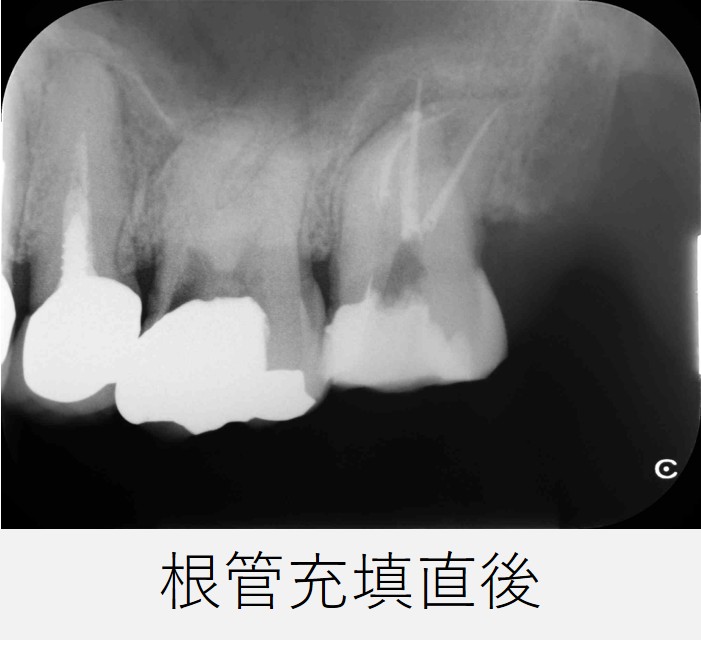

- 根管充填を行い、仮封しました。

レントゲン撮影で、根管充填の状態が良好であることを確認しました。